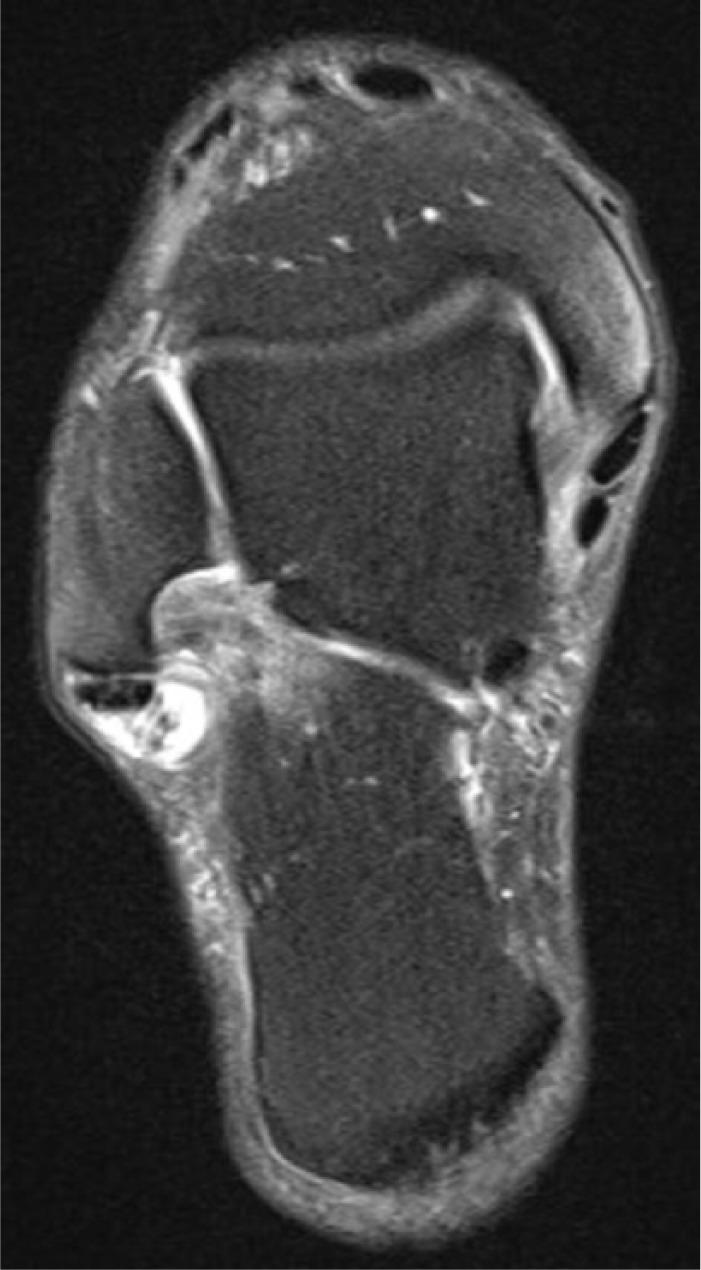

We reviewed and analysed this patient's records containing the sport-specific anamnesis, pre-existing condition, anamnesis of medications and therapy. The three injuries were magnetic resonance imaging-proven. Furthermore, the tendon's condition was examined histologically in the context of the operative treatment through lace technique of the Achilles tendon and transfer of the peroneus brevis to the peroneus longus. We also researched the literature for bilateral ruptures of the peroneal tendons.

我们回顾并分析了该患者的记录,包括运动专项病史、既往病史、用药史和治疗情况。这三处损伤均经磁共振成像证实。此外,在通过跟腱编织技术和将腓骨短肌转移至腓骨长肌进行手术治疗的过程中,对肌腱状况进行了组织学检查。我们还在文献中搜索了腓骨肌腱双侧断裂的病例。